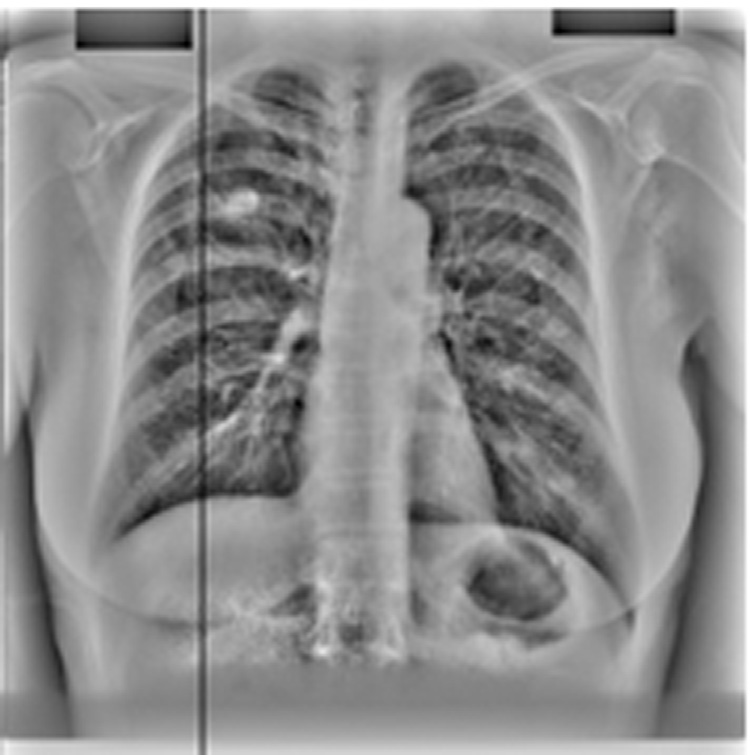

采用PCA滤波作为预处理步骤的CAD方案输出(图14.19)。PCA滤波抑制了肋骨,从而消除了发生在肋骨上的假阳性。PCA滤波还增强了被肋骨遮挡的结节。

kNN分类被添加为第三个后处理步骤,进一步将每幅图像检测到的结节数量减少至13个。图14.16展示了为JSRT数据库构建的特征空间,其中特征是之前定义的选定特征。图14.19展示了我们的计算机辅助诊断系统在kNN分类后的输出结果。

我们的最终第四种策略是将主成分分析滤波后的肋骨抑制图像作为计算机辅助诊断系统的输入。图14.20中可明显看到肋骨抑制的效果。采用主成分分析滤波后,每幅图像保留的候选结节平均数量降至三个。在肋骨边缘会检测到大量假阳性,而当输入为肋骨抑制图像时,这些假阳性被有效去除。此外,主成分分析滤波还提高了计算机辅助诊断系统的敏感性,因为被肋骨遮挡的癌结节变得更加显著。